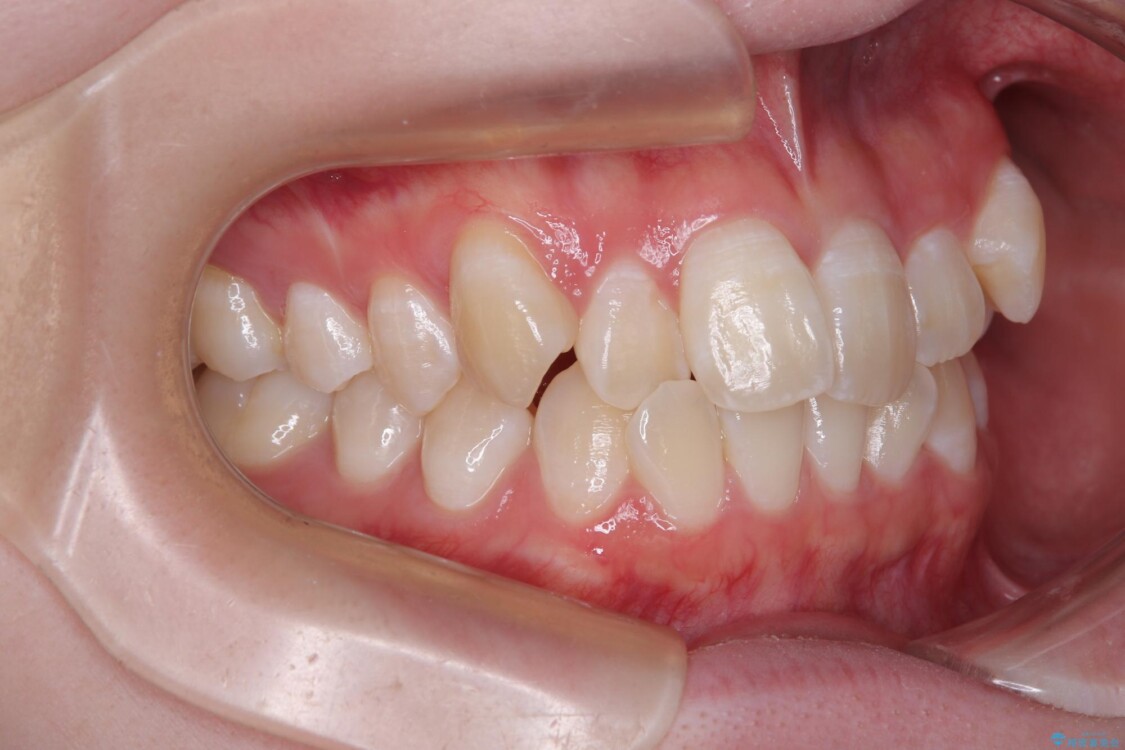

治療後

• 【モニター】前歯のデコボコをスッキリ解消!目立ちにくいワイヤー矯正でスピーディに治療完了 治療後画像

患者様の協力もあり、およそ1年間で治療を完了。スムーズな歯の移動を実現しました。

上下の正中(真ん中のライン)もずれることなく、バランスの取れた美しい歯並びに。笑顔に自信を持てる仕上がりとなりました。